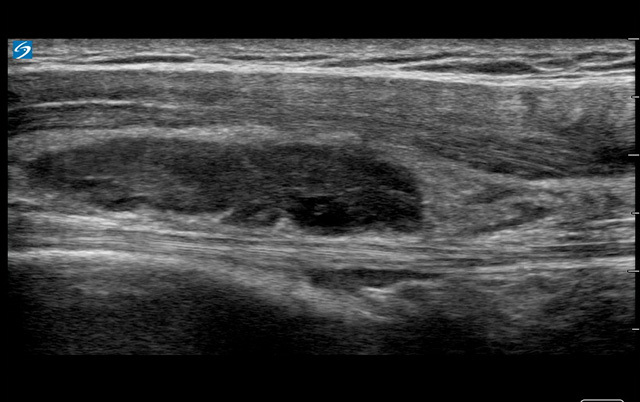

Shoulder Complex Subacromial Bursa Image